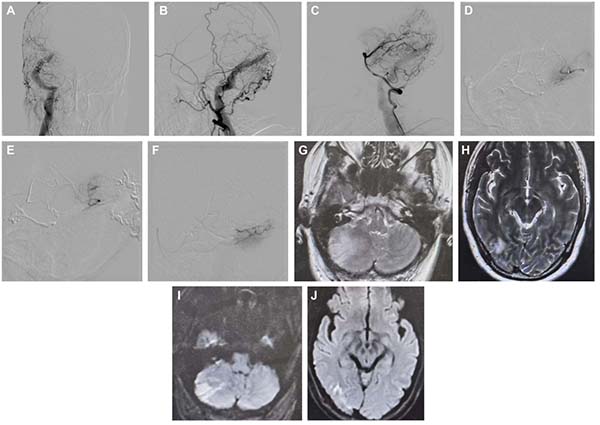

图5. A-C:该病例为右侧横窦-乙状窦区的Borden I型DAVF,可能继发于静脉窦支架植入后。患者此前曾在其他医院接受过血管内治疗。病灶区瘘口较为弥散,供血动脉来源于颈外动脉的多支硬膜分支及来自后循环的若干软膜分支。D-F:大脑后动脉和小脑上动脉的超选造影显示多条曲折的“纯”软膜及硬膜供血动脉。在栓塞过程中,将微导管尽可能置于瘘口附近,并使用Glubran进行栓塞。G-J:然而,术后MRI显示右侧小脑及枕叶出现新发梗死灶(G和H为T2加权成像;I和J为弥散加权成像)。

图6. A-C:该病例为一例位于Galen区的高级别DAVF,其供血动脉来自颈外动脉的多支硬膜分支,以及来自大脑后动脉的硬膜和“纯”软膜供血分支。D:右侧大脑后动脉的超选造影显示一条线状的硬膜供血支。E和F:此外,双侧大脑后动脉还可见曲折分支状的“纯”软膜供血支。G-I:在通过左侧PAS进行栓塞过程中,疑似发生动脉破裂。J:术后Dyna CT检查显示蛛网膜下腔出血。